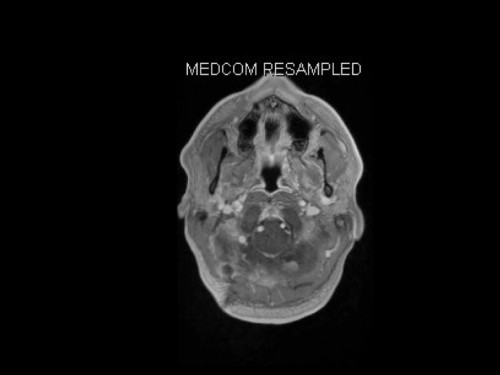

19-jähriger Mann. Er klagt seit mehreren Wochen über Schwindel und Kopfschmerzen. Im Alter von 16 Jahren sind er und sein Zwillingsbruder an einem Phäochromozytom operiert worden.